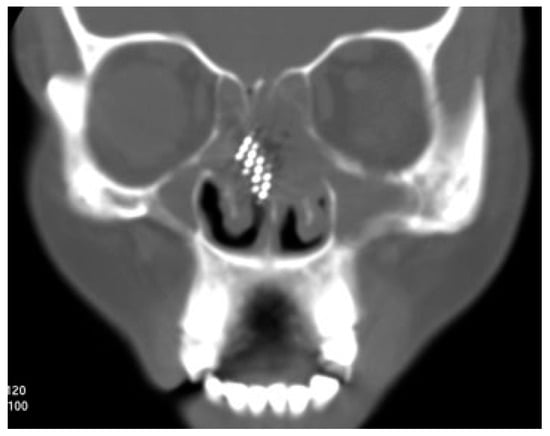

A 42-year-old woman reported to the Department of Oral and Maxillofacial Surgery with a toothbrush head lost in her nose. On careful elicitation of related events, we discovered that she had reportedly placed the tooth-brush into her nose to relieve herself of the irritable itching she was experiencing in her nose. She suffered from allergic rhinitis since childhood and frequently experienced nasal itching especially in the early morning hours. In this instance, she slipped on a wet floor and the resultant fall caused the tooth brush to snap into two pieces leaving the brush head inside the nose. The accident caused profuse nasal bleeding, which was controlled by the patient with finger pressure using a handkerchief. A computed tomographic (CT) evaluation was undertaken at a radiodiagnosis center (Figure 1) on the recommendation of a primary health care facility she had visited initially. An attempt was made at the primary health center to retrieve the brush head with a curved hemostat, which proved unsuccessful and led to a further episode of epistaxis. She was then referred to our center. She was brought to our department 3 hours after the accident. Visual inspection of the nasal cavity revealed right-sided vestibulitis with clotted blood in the right nasal cavity. The toothbrush head could not be seen on visual inspection with a nasal speculum and headlamp. Visual inspection of the pharynx was unremarkable. The patient did not complain of right nasal obstruction. The patient confirmed that she had not swallowed any portion of the object. The CT showed the presence of the toothbrush head in the superior right nasal cavity at the junction between the lateral and medial nasal walls. The brush head had caused a deviation of the nasal septum to the left (Figure 2). The patient was prepared for nasal endoscopy. The right nasal cavity was sprayed with a local anesthetic aerosol agent (lidocaine USP 15%, ICPA Health Products Ltd., Mumbai, India) and phenylephrine 0.25% applied on a cotton pellet. After 5 minutes, an endoscope was introduced into the right nasal cavity and showed a large wound in the upper part of the nasal cavity with clotted blood on the surface. No object could be identified in the nasal cavity. The patient was prepared for surgery under regional anesthesia. The patient was placed in a supine position with the head elevated ~20 degrees. The forehead, nose, and face were prepared with an antiseptic solution (2% cetavlon followed by alcohol). The nasal cavities were packed loosely with 1-cm ribbon gauze soaked in 4% lignocaine for 15 minutes. Anesthesia of the external nose was achieved using bilateral infraorbital nerve blocks (lignocaine 2% with 1:200,000 adrenaline, Xicaine, ICPA Health Products Ltd., Mumbai, India) with additional infiltrations at the base of the columella, the dorsum of the nose, the infratrochlear nerve, and the external nasal nerves, and about 0.5 mL of the solution was injected into the membranous septum. An open rhinoplasty approach with a transcolumellar extension was used. A marginal incision along the caudal border of the lateral crura of the lower lateral cartilages was made and carried medially and inferiorly along the cephalic border of the medial crus up to its lower part and then extended with a right angle turn to the caudal margin of the medial crus. A combination of sharp and blunt dissection was used to expose the entire nasal skeleton up to the nasal bones. The object was found to be lodged between the upper-right lateral cartilage and the nasal septum, with its bristles embedded into the right-upper lateral cartilage and the nasal septum (Figure 3). Dissection of the object from between the upper lateral cartilage and the nasal septum was performed after incising the upper-right lateral cartilage submucosally from the nasal cartilage and then proceeding with the exposure of the nasal septal cartilage. The object was delivered in one piece (Figure 4). Hemostasis was achieved with the use of electrocautery where indicated. Closure of the wound was achieved with polyglycolic acid 910 for the nasal mucosa and the nasal cartilages. Skin closure was achieved with prolene sutures. Bilateral nasal packs were placed. No intraoperative or postoperative complications were witnessed, and the patient was discharged on the third postoperative day.

Figure 1. Coronal computed tomography image showing position of the foreign body.